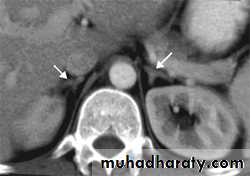

Abdominal CT: to localize the tumour.

adrenal CT should only be performed when the biochemistry supports the diagnosis of adrenal tumour.

• Conn's adenoma. A-CT scan of left adrenal adenoma (arrow). B- 131Iodo-norcholesterol scan showing uptake in left adrenal adenoma (arrow). C-The tumour is 'canary yellow' because of intracellular lipid accumulation.